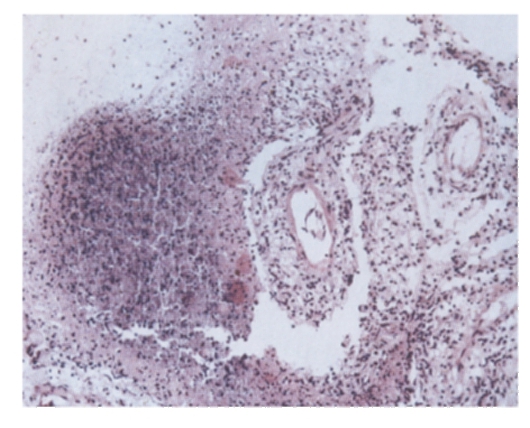

Микроскопический взгляд на мишитарный туберкулез легкого: фотодокументация

Раздел: Снимки-откровения